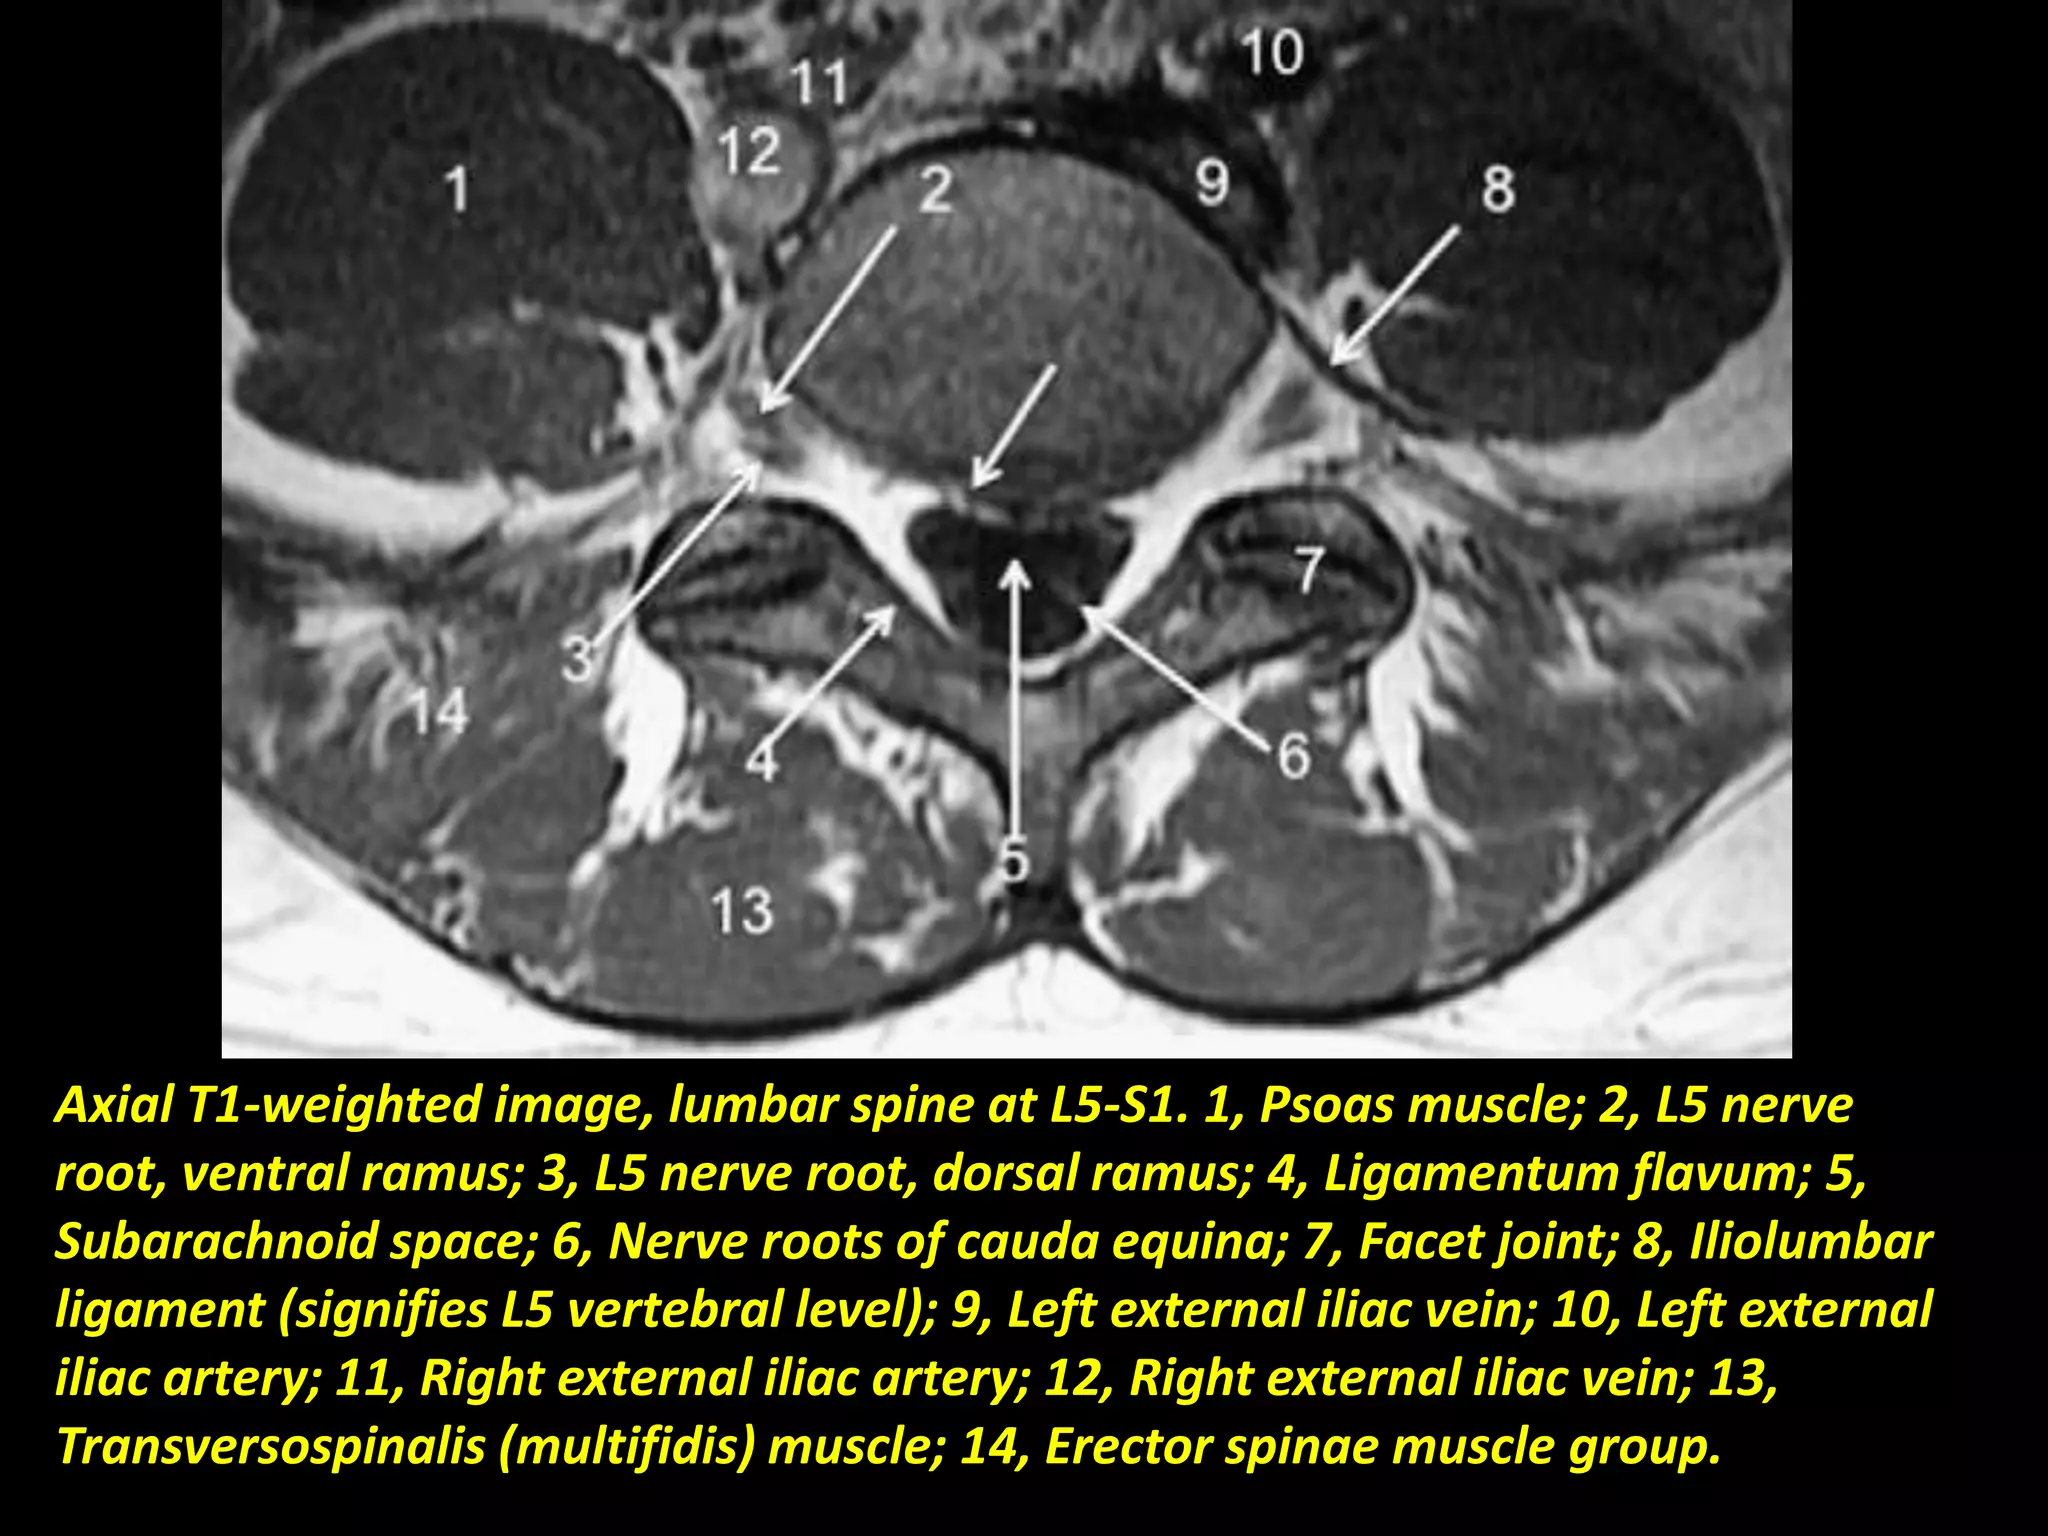

Axial T1-weighted image, lumbar spine at L5-S1. 1, Psoas muscle; 2, L5 nerve

root, ventral ramus; 3, L5 nerve root, dorsal ramus; 4, Ligamentum flavum; 5,

Subarachnoid space; 6, Nerve roots of cauda equina; 7, Facet joint; 8, Iliolumbar

ligament (signifies L5 vertebral level); 9, Left external iliac vein; 10, Left external

iliac artery; 11, Right external iliac artery; 12, Right external iliac vein; 13,

Transversospinalis (multifidis) muscle; 14, Erector spinae muscle group.

Axial T1-weighted image,lumbar spine at L5-S1. 1, Psoas muscle; 2, L5 nerve root, ventral ramus; 3, L5 nerve root, dorsal ramus; 4, Ligamentum flavum; 5, Subarachnoid space; 6, Nerve roots of cauda equina; 7, Facet joint; 8, Iliolumbar ligament (signifies L5 vertebral level); 9, Left external iliac vein; 10, Left external iliac artery; 11, Right external iliac artery; 12, Right external iliac vein; 13, Transversospinalis (multifidis) muscle; 14, Erector spinae muscle group.